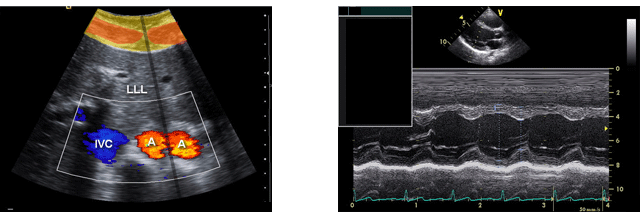

½ÉÀåÁúȯ

½ÉÇ÷°ü°è´Â ½ÉÀå°ú Àü½ÅÀÇ Å©°í ÀÛÀº Ç÷°üÀ¸·Î ±¸¼ºµÇ¸ç Ç÷¾×À» ÀÌ¿ëÇÏ¿© »ê¼Ò¿Í ¿µ¾çºÐÀ» °ø±ÞÇϰí ÀÌ»êÈź¼Ò¿Í ´ë»ç»ê¹°À» ȸ¼öÇÏ´Â ¿ªÇÒÀ» ÇÕ´Ï´Ù. ¿ì¸®³ª¶óÀÇ »ýȰȯ°æÀÌ ¼±¸È µÇ¸é¼ ºñ¸¸, ´ç´¢, °íÇ÷¾Ð, °íÁöÇ÷ÁõÀÌ ±ÞÁõÇϰí, ÀÌ·Î ÀÎÇÑ ½ÉÇ÷°ü°è ÁúȯÀÇ Áõ°¡°¡ »çȸ¹®Á¦·Î ¹®Á¦·Î ´ëµÎµÇ°í ÀÖ½À´Ï´Ù.